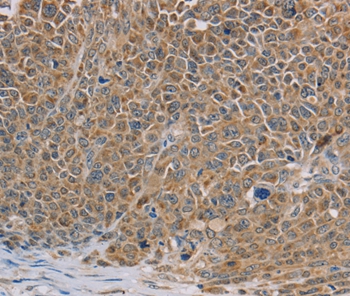

Immunohistochemical analysis of paraffin-embedded Human ovarian cancer tissue using #36642 at dilution 1/40.

应用详情:Immunohistochemistry: 1:50-1:200